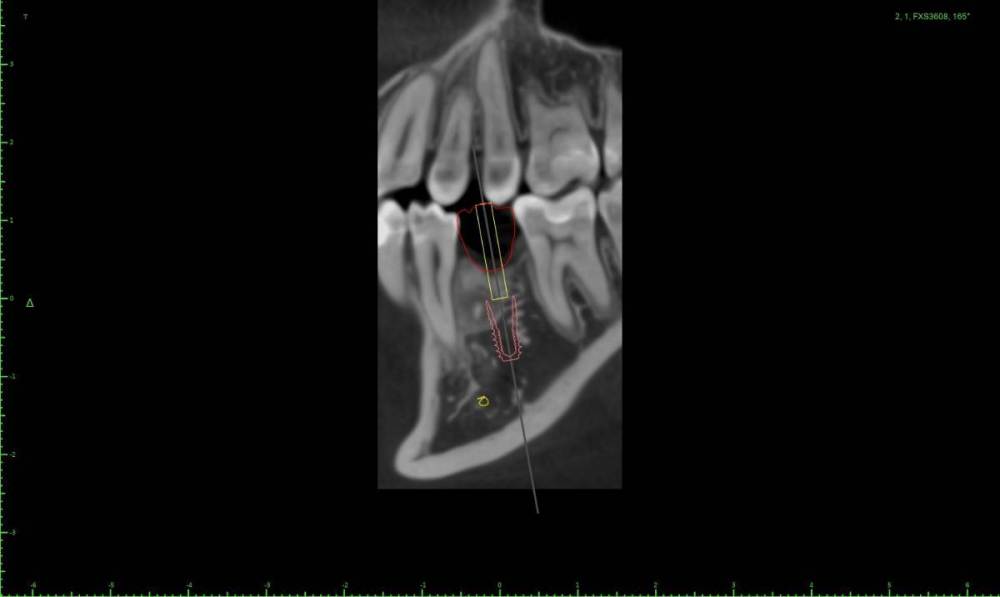

Женька Опубликовано 1 марта, 2022 Поделиться Опубликовано 1 марта, 2022 Коллеги помогайте. За качество КТ извиняйте, снимали весь череп разрешение упало у снимка. Как бы так достать его, чтобы имплантации не помешать одномоментной? Ссылка на комментарий

Irouil Опубликовано 1 марта, 2022 Поделиться Опубликовано 1 марта, 2022 Винт сместить дистальнее и чуть больше ангуляцию, примерно параллельно корням моляра соседнего судя по КТ - вестибулярно самая тонкая стенка, я бы вскрывал ее Ссылка на комментарий

Женька Опубликовано 1 марта, 2022 Автор Поделиться Опубликовано 1 марта, 2022 @Irouil тоже думал вестибулярно. Ангуляцию в сторону верхнего первого премоляра имеете ввиду? Ссылка на комментарий

Irouil Опубликовано 1 марта, 2022 Поделиться Опубликовано 1 марта, 2022 Ну да, медио-дистальную, но сохраняя выход шахты где-то в середине крестильного окна тогда в области ожидаемого дефекта кортикалки будет краешек платформы только Ссылка на комментарий